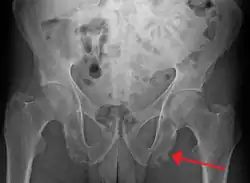

| Enthesopathy of the pelvis likely due to ankylosing spondylitis | |

An enthesopathy refers to a disorder involving the attachment of a tendon or ligament to a bone.[1] This site of attachment is known as the enthesis (pl. entheses). If the condition is known to be inflammatory, it can more precisely be called an enthesitis.

Enthesopathy can occur at the shoulder, elbow, wrist, carpus, hip, knee, ankle, tarsus, or heel bone, among other regions. Enthesopathies may take the form of spondyloarthropathies (joint diseases of the spine) such as ankylosing spondylitis, or psoriatic arthritis, plantar fasciitis, and Achilles tendinitis. Further examples include: